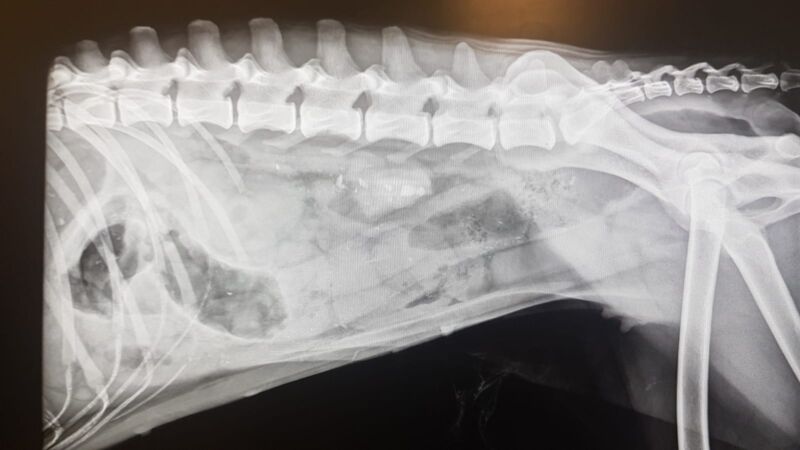

Un pezzo di plastica di discrete dimensioni poteva costare molto caro a Jackie, una bellissima cagnolina di tre anni arrivata martedì scorso nel tardo pomeriggio alla clinica veterinaria Città di Bolzano da Mezzolombardo in Trentino.

“E’ una meticcia che assomiglia molto ad un pastore del Lagorai – spiega la dottoressa Giulia Buffi che per prima l’ha accolta – e quando è arrivata presentava forte abbattimento ed anoressia. L’ho visitata e mi è sorto qualche dubbio.

Ho subito eseguito delle radiografie e un ecofast addominale (una metodica ecografica utilizzata nella medicina d’urgenza). Per me i risultati erano compatibili con l’ingestione di un corpo estraneo”.

L’operazione chirurgica – A quel punto Buffi ha chiesto un parere al dottor Tomaso Piaia che ha optato per un trasferimento immediato di Jackie in chirurgia d’urgenza. E’ stato lì che il presunto corpo estraneo è diventato molto concreto.

“Il responsabile – continua Buffi – è stato scovato a livello intestinale e ovviamente rimosso. Si trattava di un pezzo di plastica proveniente da un oggetto non identificabile nemmeno per i proprietari. E’ probabile che Jackie l’avesse ingerito da un po’ di tempo“.